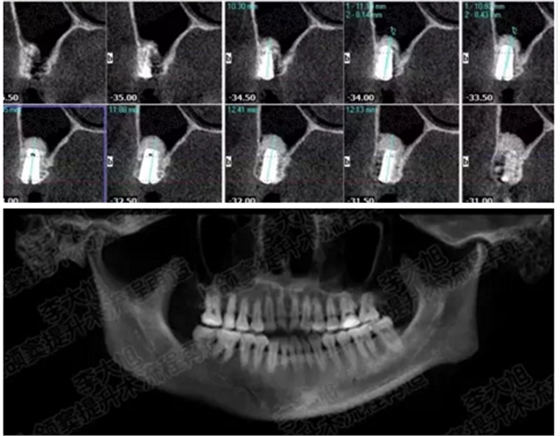

病例五

剩余不足1mm

112.png

提升10mm

113.png